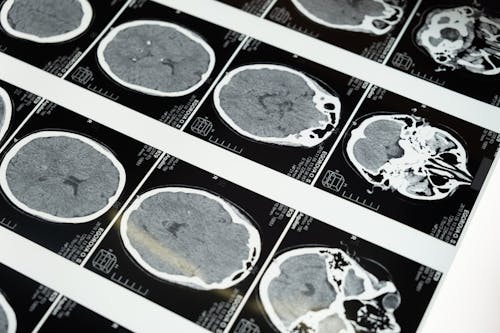

원인과 증상: 왜 기억을 잃을까?

주요 발생 원인

- 외상성 뇌 손상: 교통사고, 낙상, 폭행 등

- 뇌졸중 또는 뇌출혈